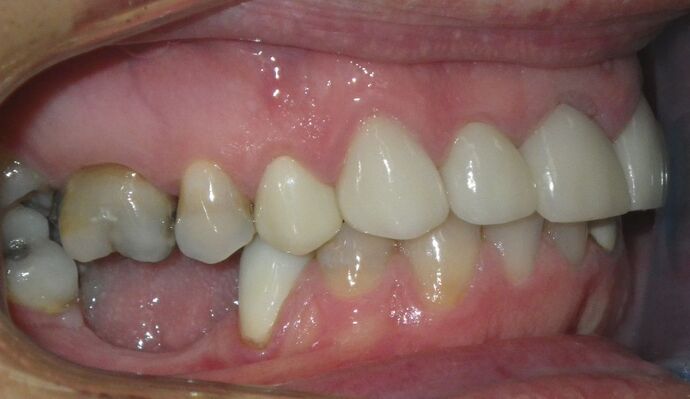

Cosmetic Changes with Veneers and Crown and Bridge: Case 5

Patient wanted to see about getting his upper front crowns replaced. He has had them for 35 plus years. Also concerns about his gums receding and the metal margins of crowns showing. Also talked with him about the need for crown lengthening which would have helped decrease the gummy smile; however, he chose not to do this. I thought just replacing the existing crowns to the existing gingival margins would be a great help. So the existing porcelain/metal crowns were removed and new all ceramic single unit crowns placed from upper right cuspid,lateral incisor and right central incisor. Then a 3-unit all ceramic bridge was placed from upper left central incisor to upper left cuspid. This patient and most of all his wife were very pleased with the end result.